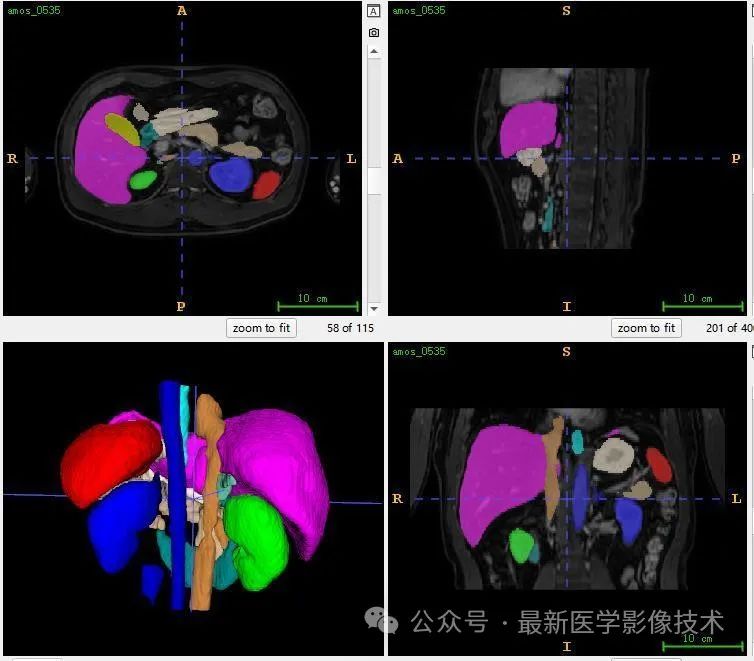

12、验证集分割结果

左图是金标准结果,右图是预测结果。

13、测试集分割结果